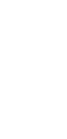

强力霉素致食管炎合并口腔溃疡及喉炎1例。

A Case of Doxycycline-Induced Esophagitis Accompanied by Oral Aphthous Ulcers and Laryngitis.